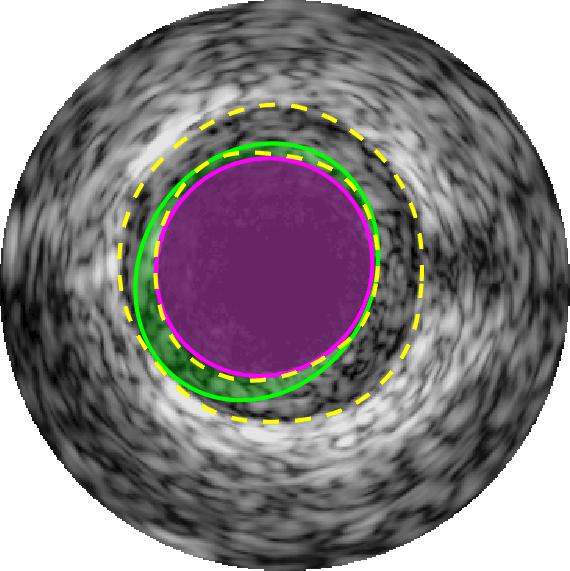

Qualitative evaluations are illustrated in Figure 4 and show the successful segmentation results of the proposed EREL selection strategy for 20 IVUS frames. The lumen areas are highlighted by the magenta colour while the media regions are green. Also, the manually annotated contours for both lumen and media are drawn as yellow dashed lines. As we can see, the chosen frames contain a variety of lumen and media morphologies.